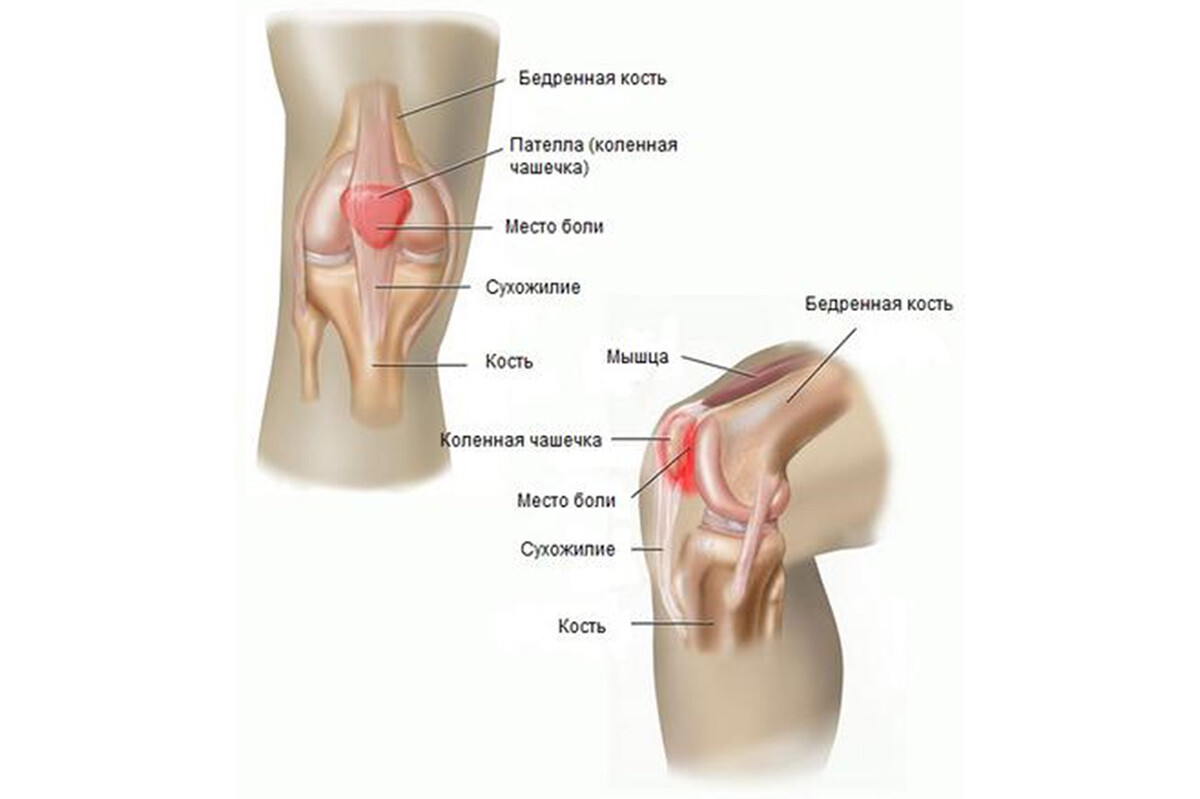

Возможные причины болей в ноге ниже колена и рекомендации